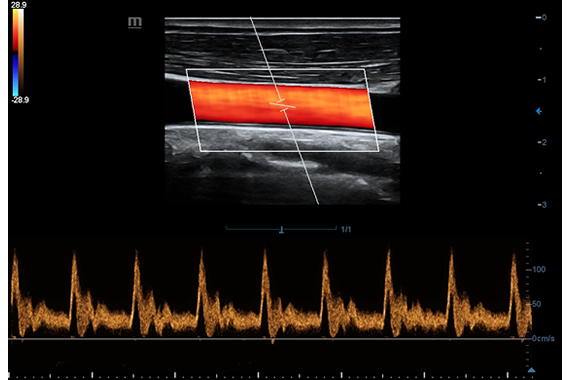

• Импульсно-волновой доплер, включая режим высокой частоты повторения импульсов HPRF.

Импульсно-волновой допплер:

Да

• Импульсно-волновой допплер (включая режим высокой частоты повторения импульсов HPRF)

• Auto IMT Package – измерения и анализ толщины комплекса интимамедии (КИМ) сонной артерии

• Vascular package - предустановленные параметры, аннотации, маркеры, программы измерений для ангиологии, включая транскраниальные исследования

• DICOM Vascular S/R - структурированный отчет по ангиологии в формате DICOM